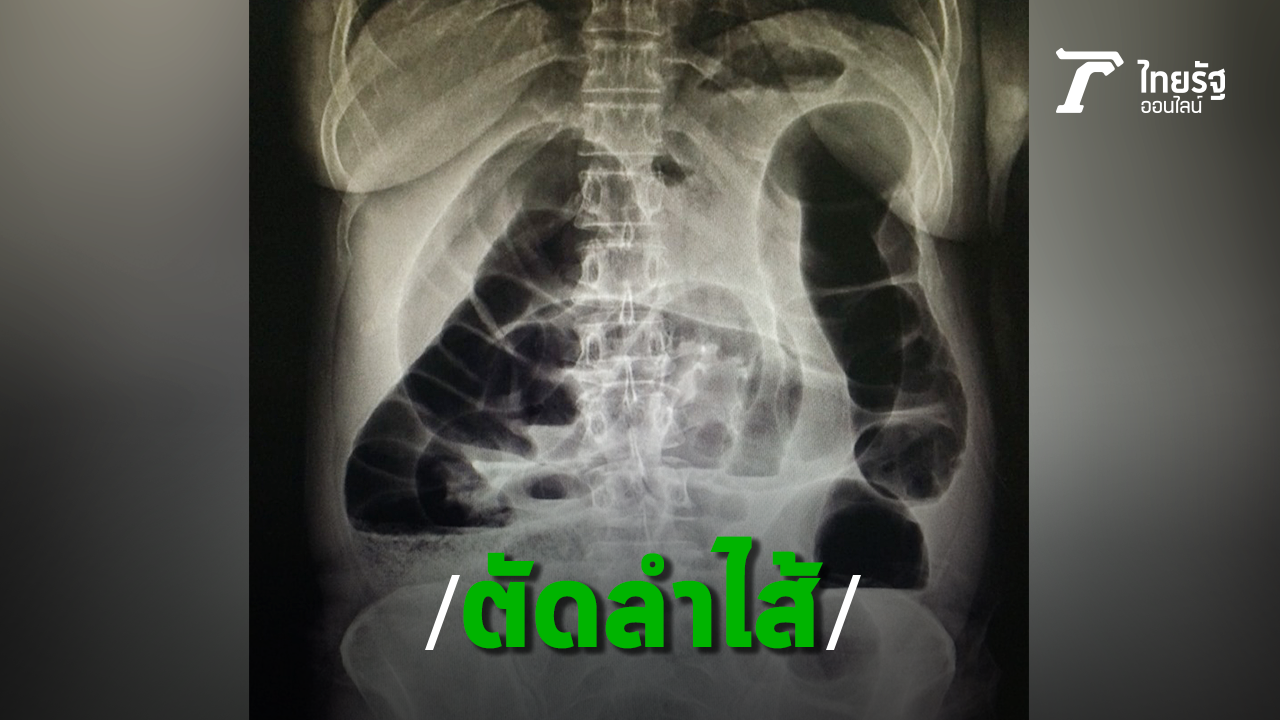

หมออารักษ์ เล่าเคสคนไข้วัย 68 ปี ท้องผูกเรื้อรัง กินยาระบาย สวนสบู่เป็นประจำ สุดท้ายลำไส้อุดตัดต้องผ่าตัดต่อลำไส้ใหม่

วันที่ 18 ส.ค.62 นพ.อารักษ์ วงศ์วรชาติ ผู้อำนวยการโรงพยาบาลสิชล จ.นครศรีธรรมราช โพสต์ภาพและข้อความเตือนภัยกรณีท้องผูกเรื้อรังจนลำไส้อุดตัน โดยยกตัวอย่าง คนไข้อายุ 68 ปี มีอาการท้องผูก 3-4 วันจึงจะขับถ่าย อุจจาระแข็ง กินยาระบาย มีการสวนสบู่เป็นประจำ

จนในที่สุดลำไส้เกิดอุดตัน มีอาการท้องอืด ท้องอืดมาก ต้องเข้ารับการผ่าตัดฉุกเฉินตัดลำไส้บางส่วนที่โป่งพองอย่างมากทิ้งไป แล้วต่อลำไส้ใหม่ "ท้องผูกเรื้อรัง จึงไม่ใช่ภาวะปกติที่ปล่อยวางได้".